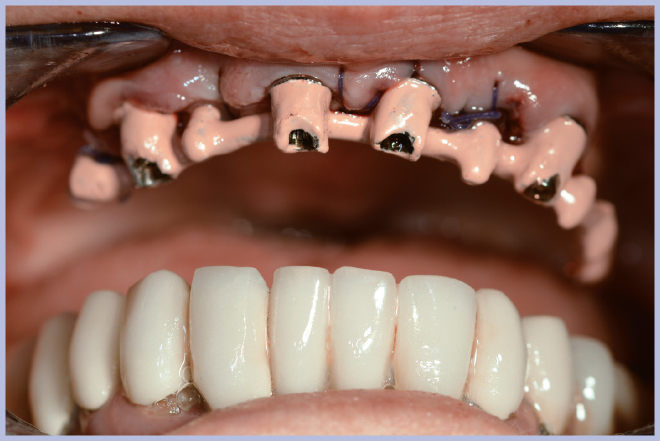

Sui monconi, dopo aver attivato la connessione a cono Morse (Fig. 3), sono state fissate le apposite cappette in titanio con le viti a testa alta (Fig. 4) ed è stata realizzata un’armatura di rinforzo per mezzo di una sincristallizzatrice intra-orale. In particolare la barra è stata ottenuta mediante saldatura sulle cappette di un filo pre-modellato di titanio grado 2 (Figg. 5, 6).

- Figg. 5, 6 – Struttura di rinforzo ottenuta saldando intra-oralmente un filo di titanio alle cappette

- Fig. 6